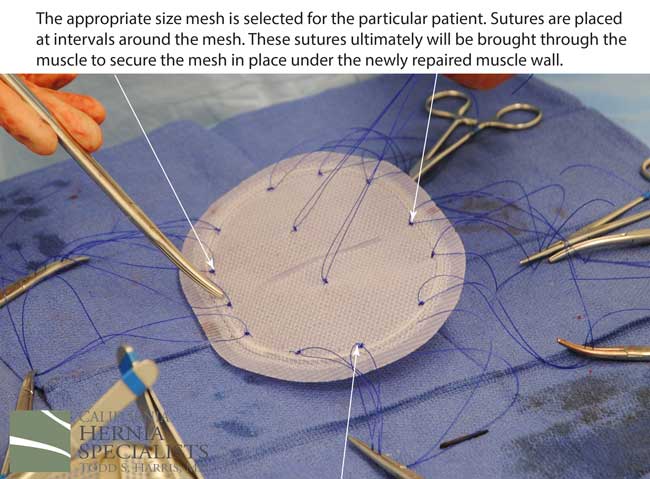

The more complete approach would be to bring healthy muscle together at the mid line. Only after the muscle is repaired completely, can a mesh be used to SUPPORT the muscle repair. Meshes should not be considered a bridge from healthy muscle to healthy muscle. Instead mesh should be used as a reinforcement of a correct hernia repair.

This technique requires more surgical time, recovery time, and usually several days in the hospital. However, this patient chose to proceed with the open hernia repair. Below are some of the pictures from his surgery as well as post operative CT scan image and photos of the patient.

Since the abdominal muscles were weakened, we placed a sheet of biologic mesh under the muscle in the middle at the area of the hernia hole, closed the muscle over this mesh, then placed another mesh on top of the muscles which were closed. This provided him with three layers of repair.